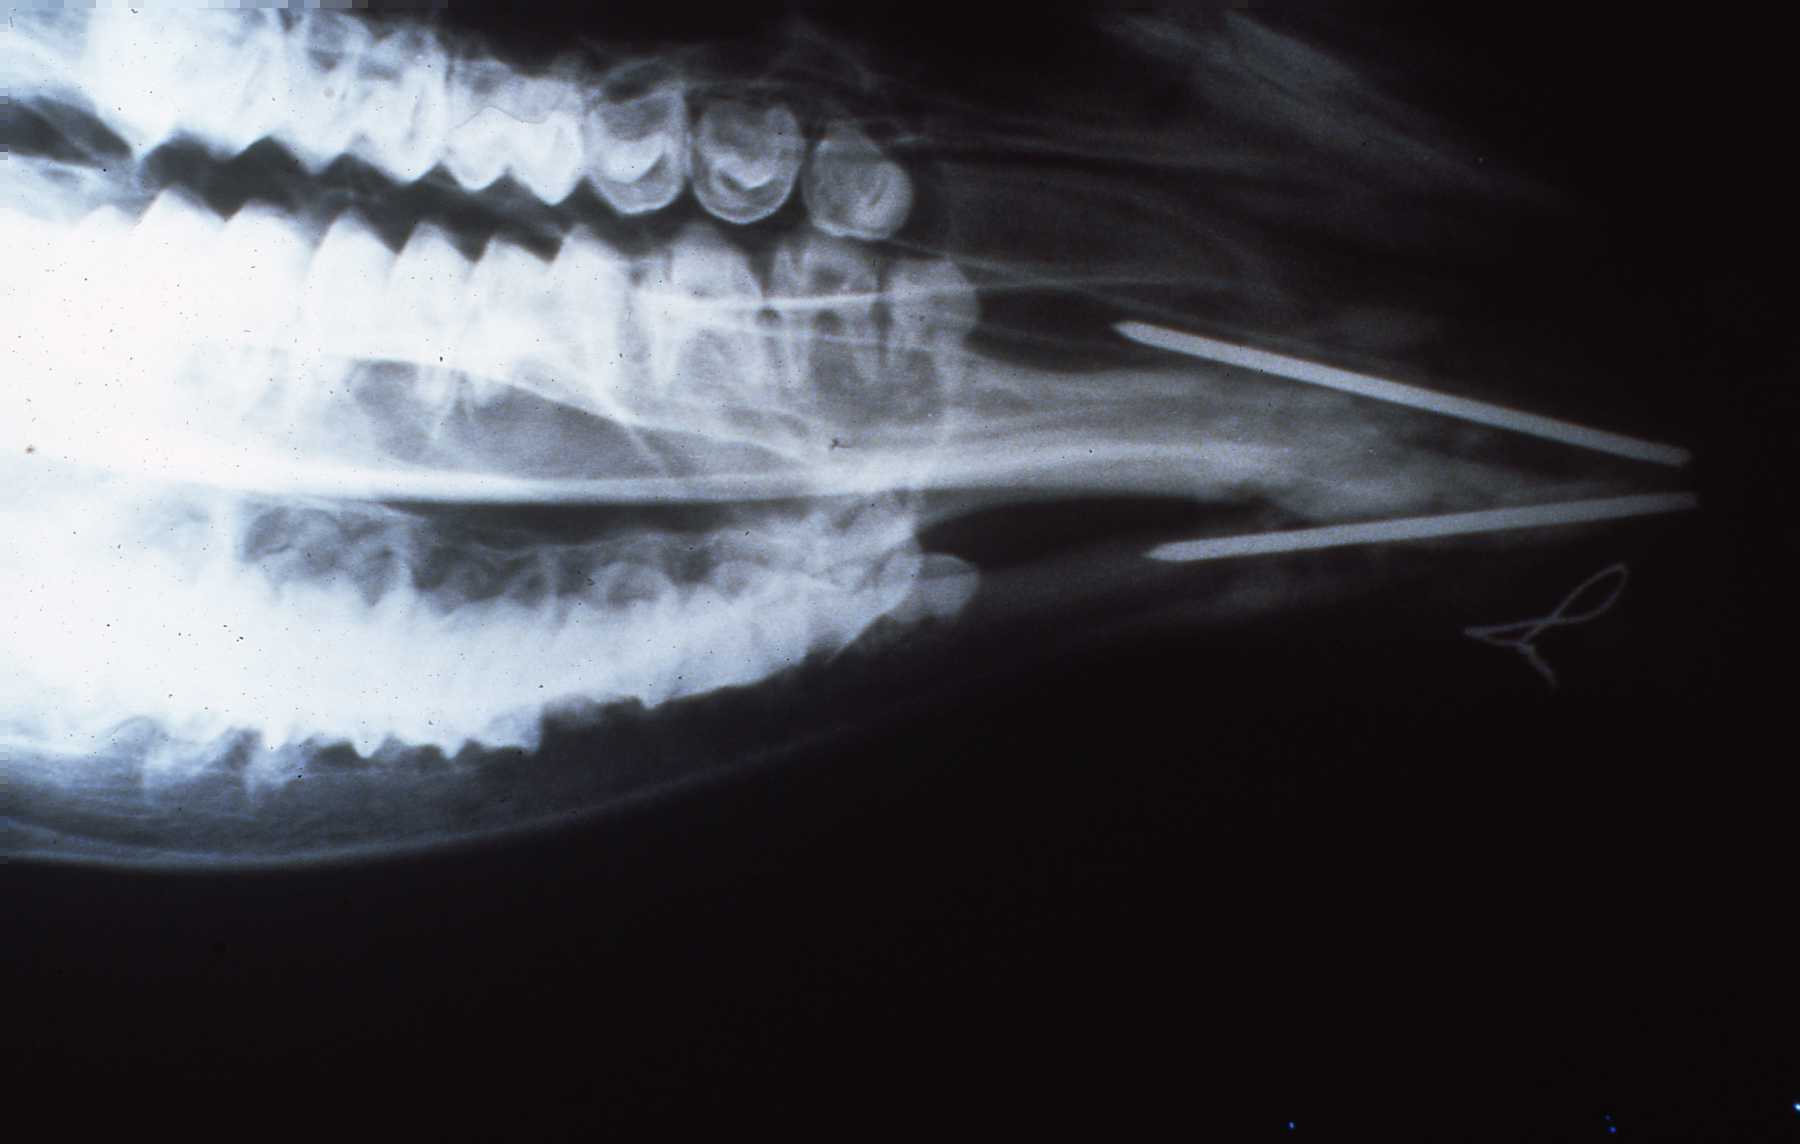

Initial radiograph, taken after I had removed the small first premolar. Purulent exudate flowed out of alveolus. Fracture line along mesial border of second premolar. Antibiotics administered, animal allowed to recover while we discussed further treatment.

Radiograph prior to extraction of premolar.